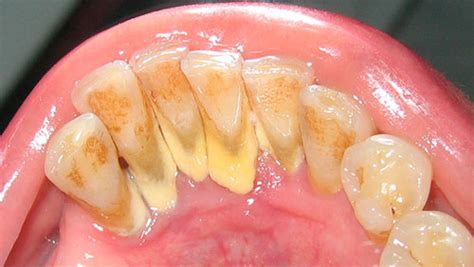

El sarro es por tanto resultado del endurecimiento de esa placa bacteriana no retirada. Forma un recubrimiento blanquecino o amarillento en la base de los dientes, en especial en los dientes inferiores anteriores por el lado de la lengua y en los molares superiores por el lado de la mejilla. La placa puede eliminarse mediante el cepillado diario, sin embargo, el sarro no puede eliminarse mediante cepillado y solo pueden eliminarlo adecuadamente un dentista o un higienista dental.

El sarro tiene la apariencia de una costra gruesa que cubre los dientes, sobre todo la parte trasera de las piezas delanteras inferiores, que es una zona más difícil de limpiar. También puede formarse entre las piezas dentales y el borde de las encías.

Inicialmente su color es blanquecino, pero se mancha con facilidad y puede adquirir un tono amarillento o amarronado. Asimismo, puede presentarse acompañado de hinchazón y enrojecimiento de las encías, cuadro conocido como gingivitis.

- Supragingival. Se acumula en la superficie visible de los dientes y encías.

- Subgingival. Se localiza por debajo de la línea de la encía, por lo que es más difícil de percibir.